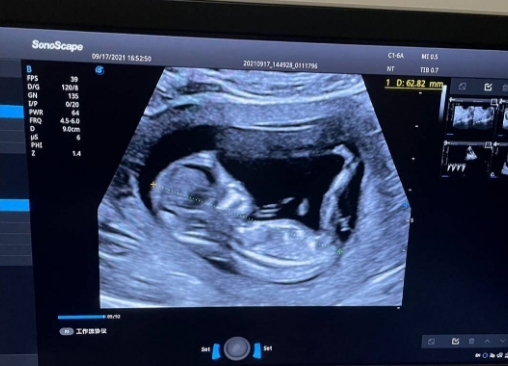

12周男宝生殖图多通过超声检查获取,其呈现效果受多种因素制约,识别准确性有限。超声设备分辨率、胎儿体位、羊水量多少等,都会直接影响生殖结构的显示清晰度,部分情况下可能因胎儿肢体遮挡、蜷缩姿势导致观察不全。此时男宝生殖器官尚未完全发育,生殖结节与女性胎儿的阴蒂雏形相似度较高,即使是经验丰富的医生,超声识别准确率也仅约70%,完全无法作为性别判断的可靠依据,更不能仅凭生殖图下定论。

12周男宝生殖图的核心意义的是辅助产检,评估生殖系统发育情况,而非辨别性别。医生通过生殖图观察生殖结节形态、睾丸位置及发育状态,排查是否存在生殖器官发育畸形的早期迹象,为后续孕期保健提供参考。同时,结合超声其他指标,能全面判断胎儿整体发育进度,及时发现潜在健康问题。孕妈需明确,生殖图是医疗评估工具,其价值在于守护胎儿健康,而非满足性别好奇。